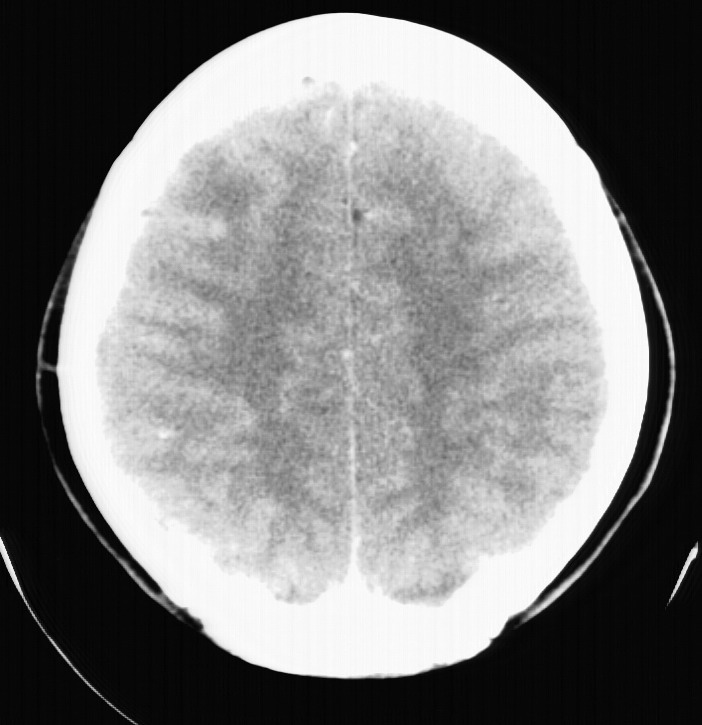

标题: CT5853:右额叶上部占位请会诊

女,34岁,自述头晕胀2年,近期感精神恍惚,无发热,实验室检查阴性。

右顶叶靠近脑表面圆形低密度灶,周围无水肿及占位效应,增强病灶无明显强化,考虑:右顶叶低分级星型细胞瘤。

右额叶上部皮质区见类圆形低密度区,边界不清,无强化,无钙化。

支持大多数战友的意见,1级星形细胞瘤。